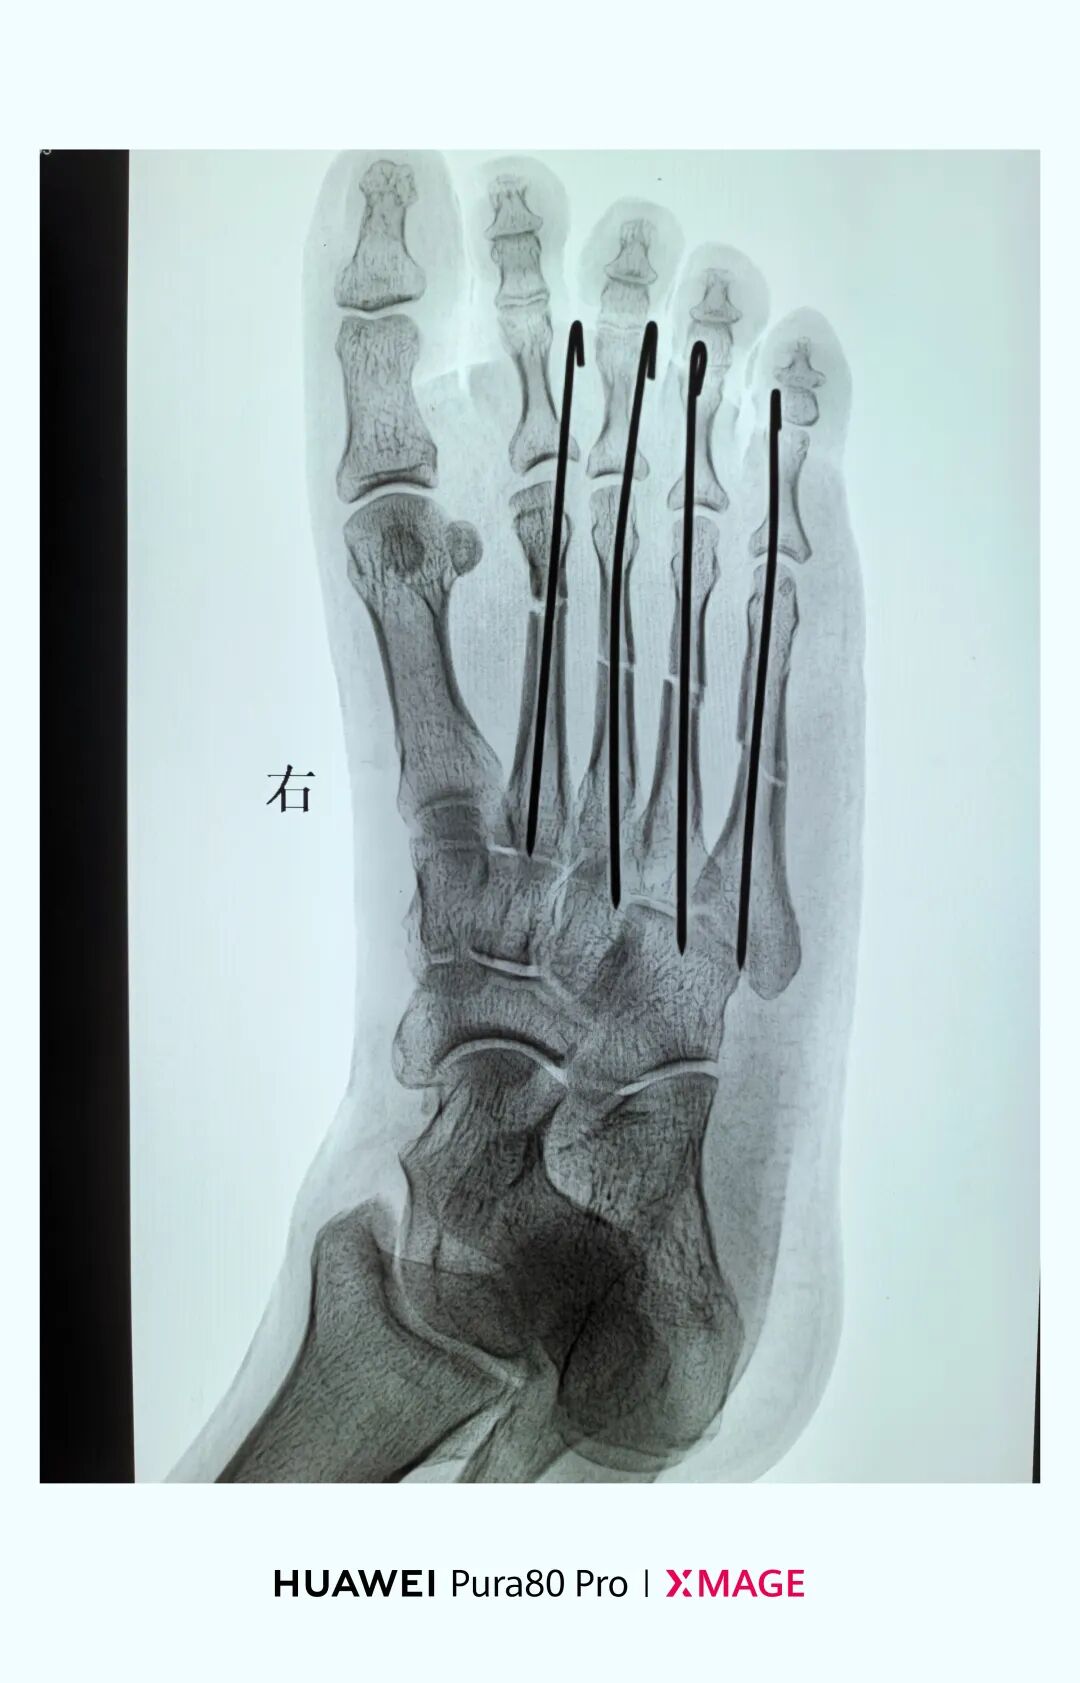

跖骨骨折常伴严重软组织损伤,治疗需兼顾骨性稳定与软组织保护。逆行髓内克氏针技术以微创方式实现有效内固定,尤其适用于多发骨折、开放损伤或软组织条件差的患者。其操作简便、血运破坏少,在损伤控制中展现独特优势。本文通过四例典型病例,探讨该技术在闭合性、开放性及严重毁损伤中的临床应用价值。

闭合性2-5跖骨骨折

逆行髓内针